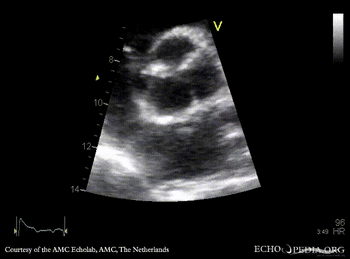

Endocarditis of aortic valve

A4CH: dilated left ventricle A5CH: vegetations on aortic valve, dilated left ventricle